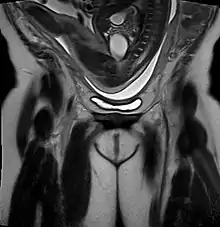

Breech birth position seen on MRI

As in labour with a baby in a normal head-down position, uterine contractions typically occur at regular intervals and gradually the cervix begins to thin and open.[32] In the more common breech presentations, the baby's bottom (rather than feet or knees) is what is first to descend through the maternal pelvis and emerge from the vagina.[24]